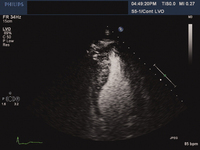

Cardiomiopatia dilatada: ecocardiografia

Tanejal AK, Wong J, Bayliss J. Antipsychotic-drug-induced dilated cardiomyopathy. BMJ Case Reports. 2009; doi:10.1136/bcr.09.2008.0958